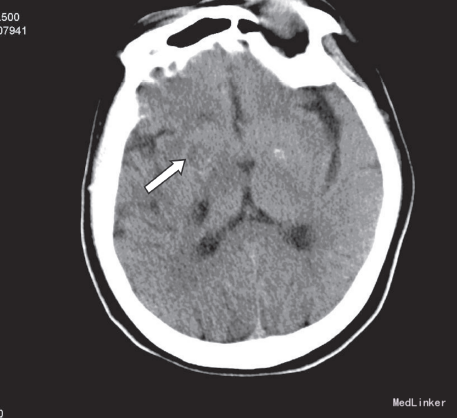

入院查体:T:36.5℃,P:100 次/分,R:20次/分,BP:141/81mmHg。神志清楚,反应迟钝,查体合作。双瞳孔等大等圆,直径0.3cm,对光反射存在,眼球活动正常,额纹对称,嘴角无歪斜,伸舌居中,颈软。左上肢肌力1级,左下肢肌力2+级,左侧肢体肌张力及腱反射减弱。右侧肢体肌张力、肌力及腱反射正常。双侧浅感觉正常,病理征阴性。人院后完善相关检查,急诊头部CT平扫示:右侧基底节区多发斑片状低密度影,内密度欠均匀见图诊断为脑梗塞。